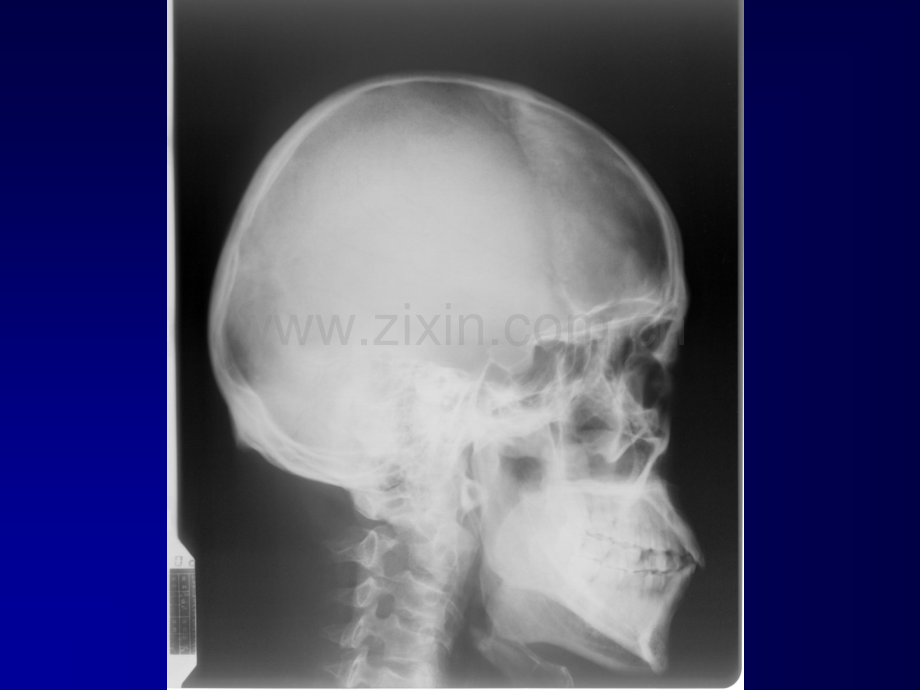

神经系统见习神经系统见习脑脑梗梗塞塞Infarctus cerebralT1WT1WT2WT2WInfarctus cerebralCTMRIUneUne patientepatiente lage de 50 lage de 50 ansansInfarctus cerebral48-year-old male patient48-year-old male patientLa contusion crbraleAcute subdural hematomaLa fracture鼻咽癌 病因:未完全明确,与慢性炎症、移传和EB病毒感染 有关 病理:最常见为鳞状上皮癌,其次是未分化癌和低分 化癌 临床表现:回缩涕带血、鼻塞、颈部淋巴结增大、听力 下降、耳鸣、头痛和复视等 鼻咽癌 鳞状上皮癌占鼻咽恶性肿瘤的90。生于鼻咽侧壁,占据咽隐窝(fossa of Rosenml1er),阻塞咽鼓管。常见症状为浆液性耳炎和颈部转移性肿块。有这些症状者影像检查应包括鼻咽部。鳞癌早期就穿破咽颅底筋膜侵入咽旁间隙和颅底。胸锁乳突肌后的颈后三角区常可发现淋巴结转移 甲状腺正常CT表现 分左右两叶位于环状软骨下方、气管两旁,中间以峡部相连,侧叶上缘平甲状软骨中点,下极达第六气管环平面。边缘光整,密度均匀且密度较高,CT值在70Hu左右,是人体内正常软组织密度最高的器官;注射造影剂后强化效应明显。扫描方法同喉部CT扫描。思考题思考题颅脑肿瘤的占位效应体现在哪些方面?颅脑肿瘤的占位效应体现在哪些方面?颅脑外伤有几种常见类型?颅脑外伤有几种常见类型?脑梗塞和脑出血的影像学表现特点?脑梗塞和脑出血的影像学表现特点?